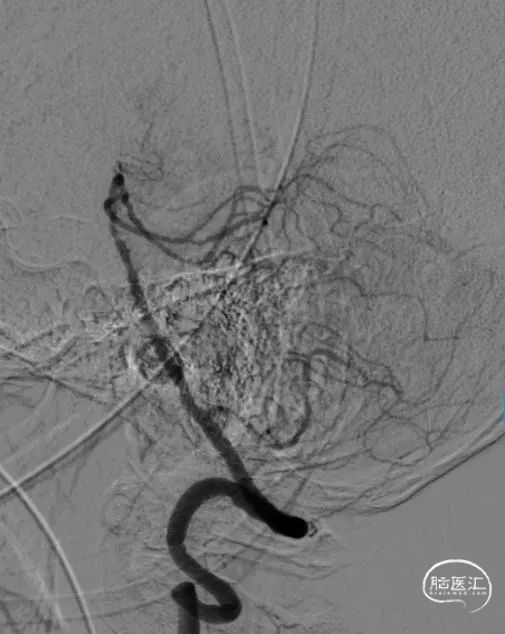

术中DSA

4.0*30mm Syphonet®取栓支架锚定

2.0*15mm 球囊扩张